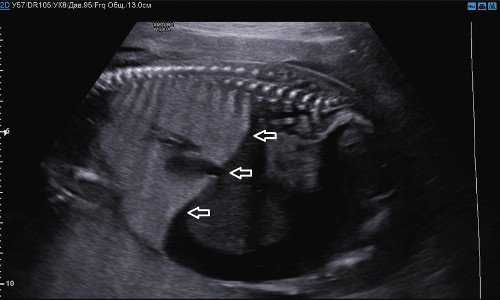

Также обращал на себя внимание выраженный асцит и инверсия купола диафрагмы (рис. 2, 3).

Рис. 2. Поперечный скан. Выраженный асцит.

Рис. 3. Парасагиттальный скан. Выраженный асцит и инверсия купола диафрагмы (стрелки).